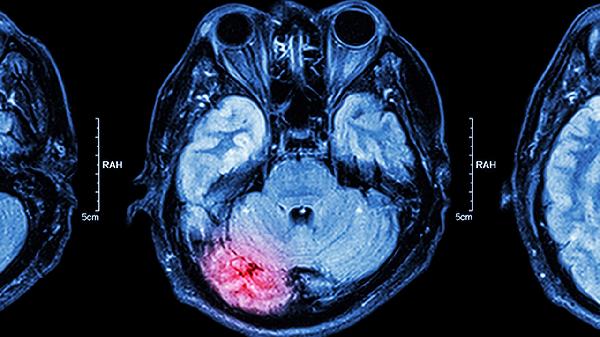

尼莫地平片是一种钙通道阻滞剂,能够选择性扩张脑血管,增加脑血流量,直接改善脑部缺血状态。它对于脑血管痉挛引起的脑供血不足有较好的效果。使用时应严格按照医嘱,注意可能引起的血压下降等反应。